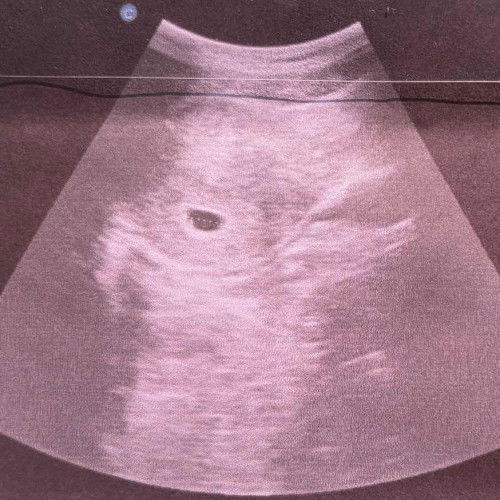

ตอนนี้6w5d ช่วยดูได้มั้ยคะว่าสีขาวๆในถุงตั้งครรภ์ใช่ตัวอ่อนหรือถุงไข่แดงมั้ย 1อาทิตย์ที่แล้วซาวด์ดูถุงตั้งครรภ์0.93 อาทิตย์นี้1.58 ใหญ่ขึ้น มีโอกาสท้องลมมั้ยคะ หมอนัดอีกทีเดือนหน้าเลยค่ะ เครียดค่ะ😣